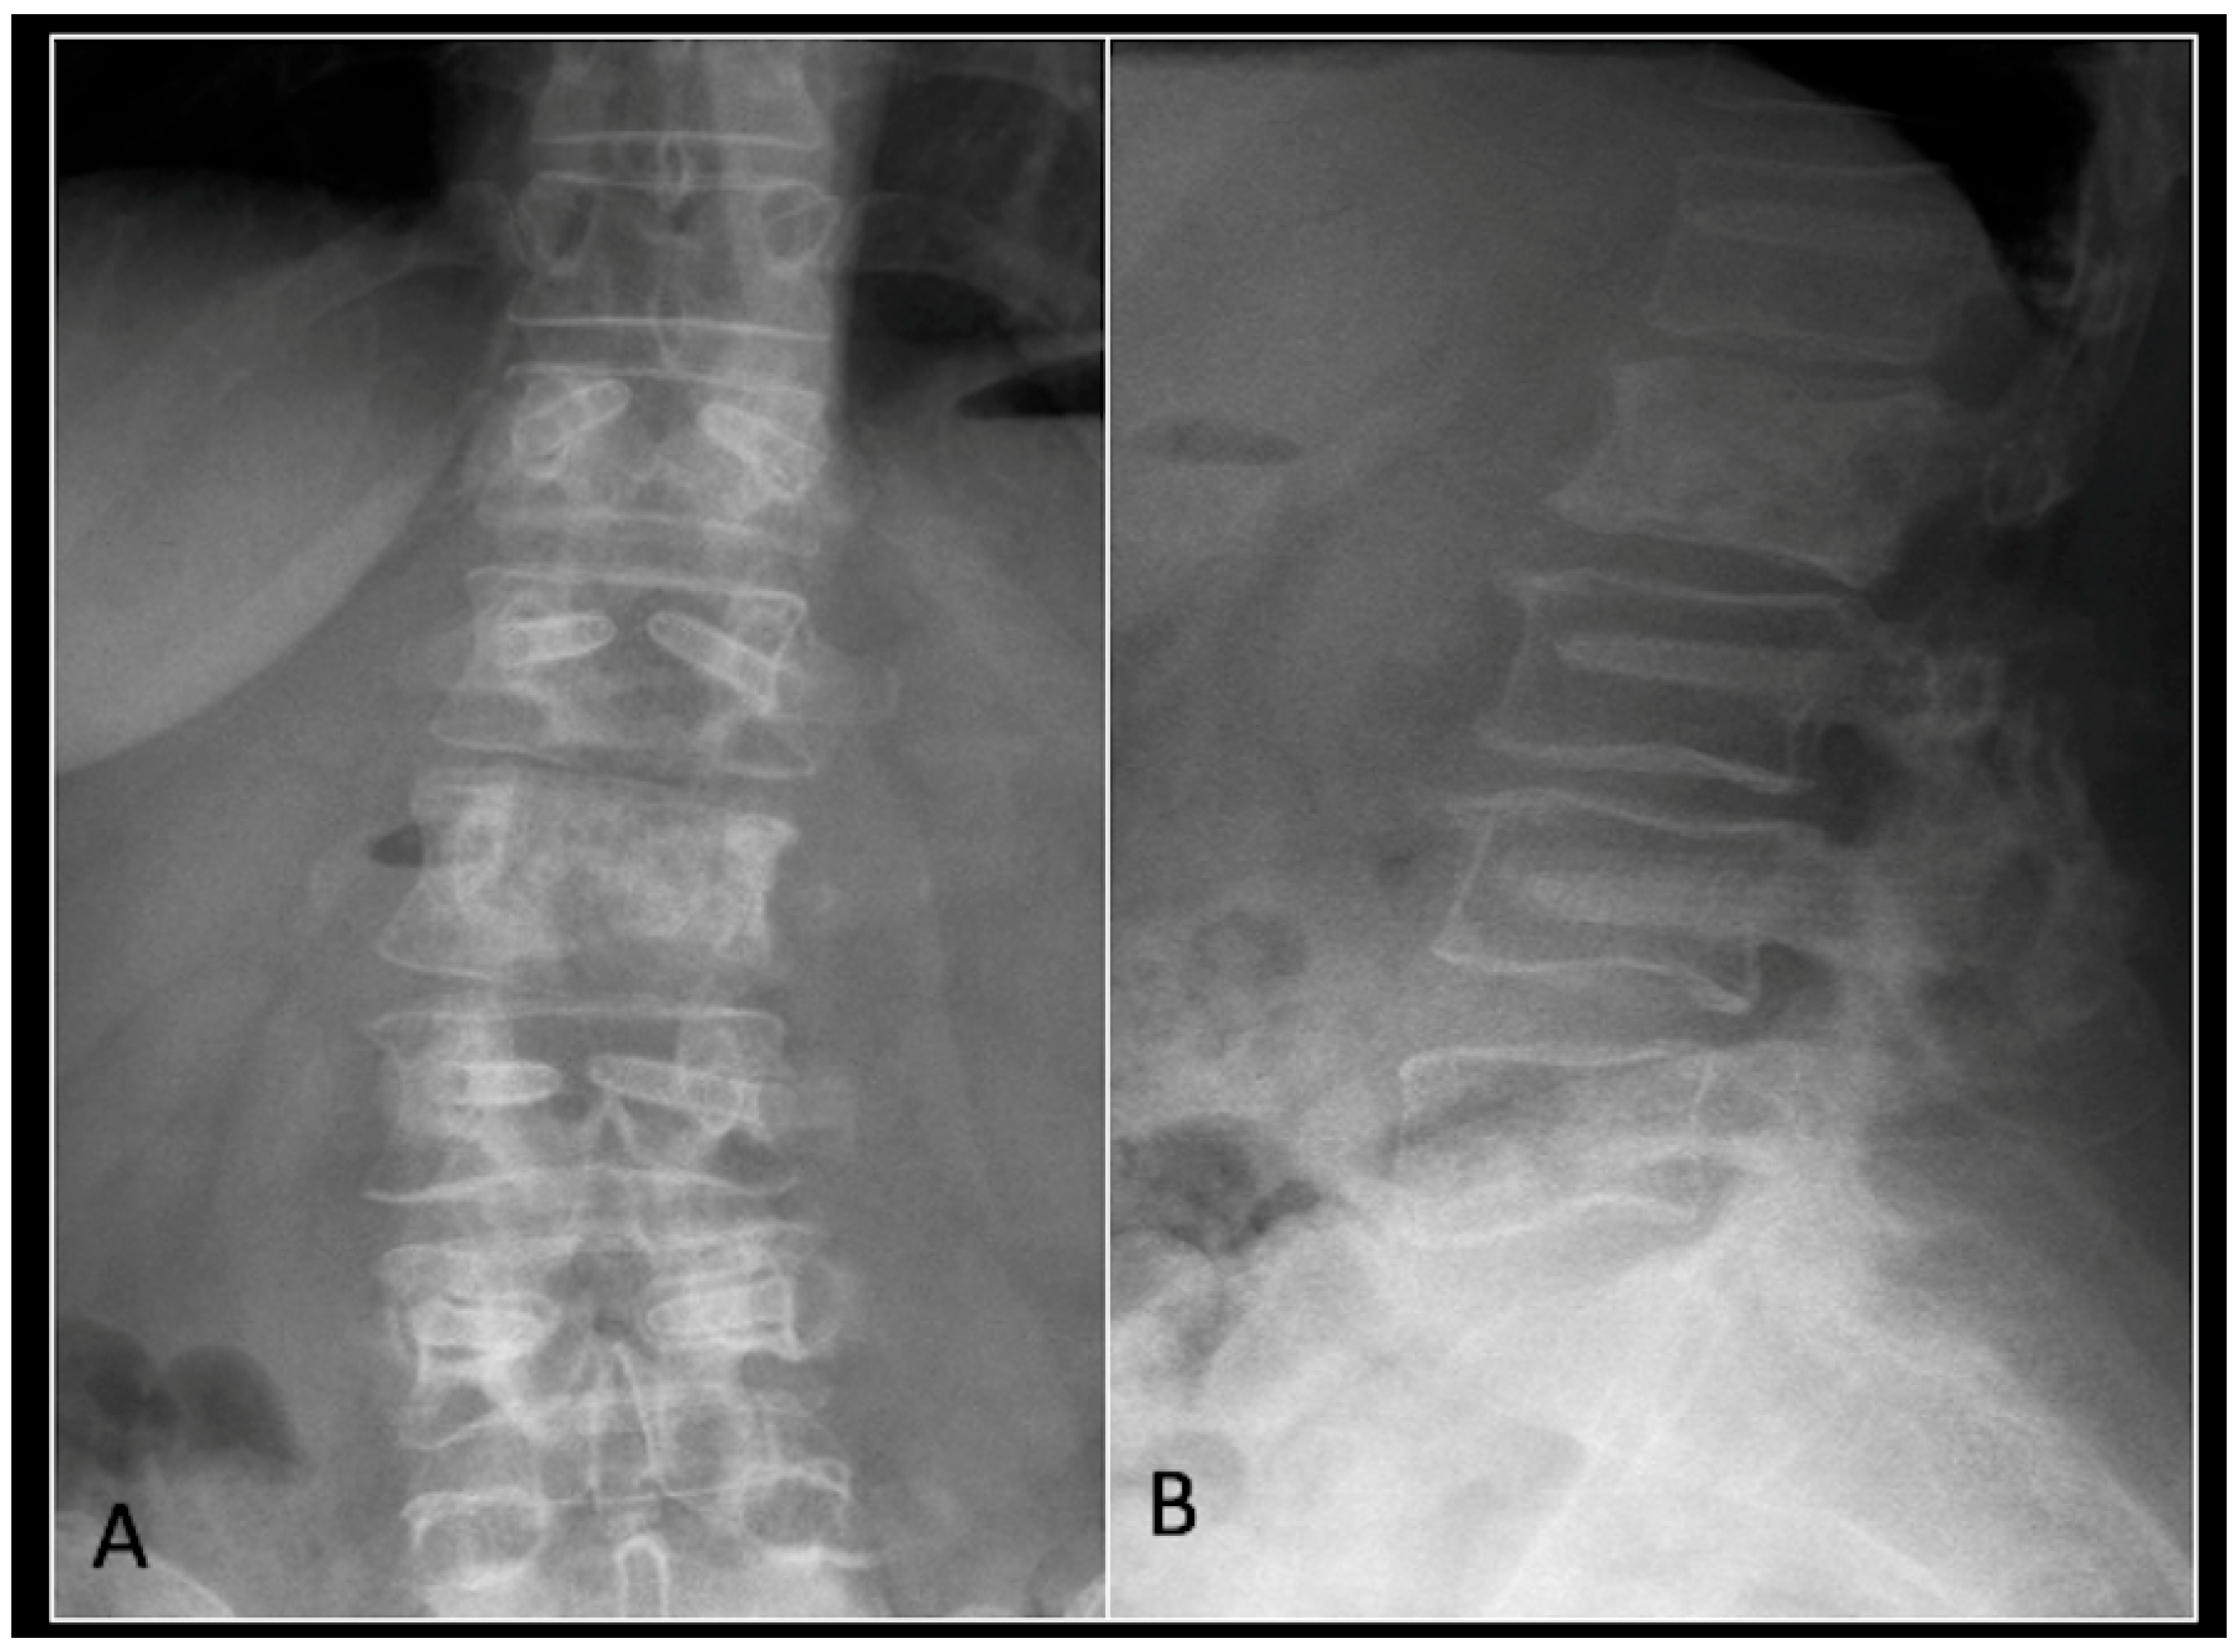

2.4. Case 4: Lumbar Chordoma

This 56-year-old lady was diagnosed with a biopsy-confirmed L2 chordoma (Figure 11). She underwent posterior decompressive separation surgery and instrumental stabilisation T12-L4 using carbon-based implants (Figure 12). Surveillance imaging at 6 months and 12 months post-separation did not show any progression of residual tumour disease (Figure 13 and Figure 14).

Figure 11.

RI demonstrating a lobulated destructive lesion (arrow) with significant epidural extension and compression at L2. The yellow line on the sagittal images denotes the level of the axial image. (A) T2W sagittal; (B) T1W sagittal; (C) T2W axial.

Figure 12.

(A) demonstrates an anteroposterior view, and (B) illustrates a lateral standing radiograph of the lumbosacral spine demonstrating carbon-based posterior instrumentation.